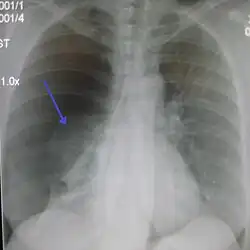

Chest X-ray

A plain chest radiograph, ideally with the X-ray beams being projected from the back (posteroanterior, or "PA"), and during maximal inspiration (holding one's breath), is the most appropriate first investigation.[35] It is not believed that routinely taking images during expiration would confer any benefit.[36] Still, they may be useful in the detection of a pneumothorax when clinical suspicion is high but yet an inspiratory radiograph appears normal.[37] Also, if the PA X-ray does not show a pneumothorax but there is a strong suspicion of one, lateral X-rays (with beams projecting from the side) may be performed, but this is not routine practice.[18][22]

It is not unusual for the mediastinum (the structure between the lungs that contains the heart, great blood vessels, and large airways) to be shifted away from the affected lung due to the pressure differences. This is not equivalent to a tension pneumothorax, which is determined mainly by the constellation of symptoms, hypoxia, and shock.[16]

The size of the pneumothorax (i.e. the volume of air in the pleural space) can be determined with a reasonable degree of accuracy by measuring the distance between the chest wall and the lung. This is relevant to treatment, as smaller pneumothoraces may be managed differently. An air rim of 2 cm means that the pneumothorax occupies about 50% of the hemithorax.[18] British professional guidelines have traditionally stated that the measurement should be performed at the level of the hilum (where blood vessels and airways enter the lung) with 2 cm as the cutoff,[18] while American guidelines state that the measurement should be done at the apex (top) of the lung with 3 cm differentiating between a "small" and a "large" pneumothorax.[38] The latter method may overestimate the size of a pneumothorax if it is located mainly at the apex, which is a common occurrence.[18] The various methods correlate poorly but are the best easily available ways of estimating pneumothorax size.[18][22] CT scanning (see below) can provide a more accurate determination of the size of the pneumothorax, but its routine use in this setting is not recommended.[38]

Not all pneumothoraces are uniform; some only form a pocket of air in a particular place in the chest.[18] Small amounts of fluid may be noted on the chest X-ray (hydropneumothorax); this may be blood (hemopneumothorax).[16] In some cases, the only significant abnormality may be the "deep sulcus sign", in which the normally small space between the chest wall and the diaphragm appears enlarged due to the abnormal presence of fluid.[19]

Computed tomography

CT with the identification of underlying lung lesion: an apical bulla on the right side

A CT scan is not necessary for the diagnosis of pneumothorax, but it can be useful in particular situations. In some lung diseases, especially emphysema, it is possible for abnormal lung areas such as bullae (large air-filled sacs) to have the same appearance as a pneumothorax on chest X-ray, and it may not be safe to apply any treatment before the distinction is made and before the exact location and size of the pneumothorax is determined.[18] In trauma, where it may not be possible to perform an upright film, chest radiography may miss up to a third of pneumothoraces, while CT remains very sensitive.[21]

A further use of CT is in the identification of underlying lung lesions. In presumed primary pneumothorax, it may help to identify blebs or cystic lesions (in anticipation of treatment, see below), and in secondary pneumothorax, it can help to identify most of the causes listed above.[18][22]